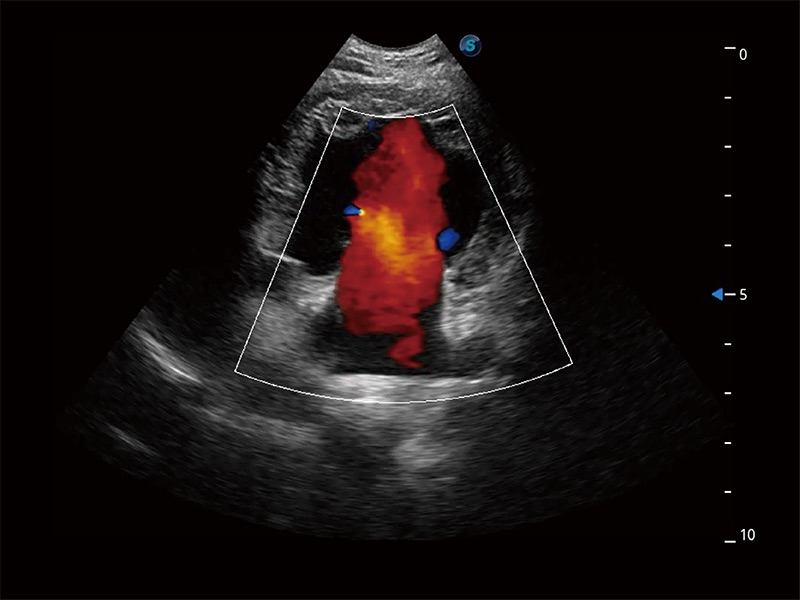

在传统二维血流成像的基础上,呈现血流的立体感,具有动感的生命力之美。即便是微小的血管也能轻松应对,提高了血流的视觉敏感性。

ProPet 80 配备了丰富的心脏探头群、先进的成像技术和专业的心脏测量工具,可帮助动物医生为不同体型和生理结构的动物提供心脏和心肌功能的全面评估。

实时用颜色表示心肌组织运动,观察和定量组织的运动情況,对快速检测与评估心肌的灌注和活性、电传导及心肌收缩和舒张功能等均能提供重要的诊断信息。